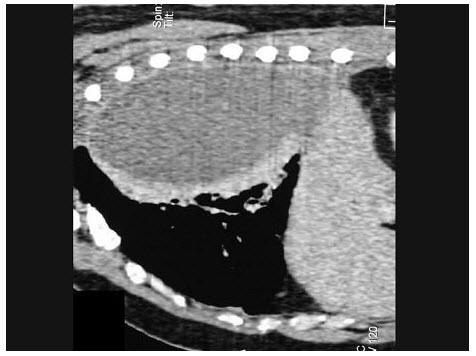

男,76岁,无痛性肉眼血尿3个月,CT检查如图所示,下列说法错误的是()

A.左侧肾盂扩张积水